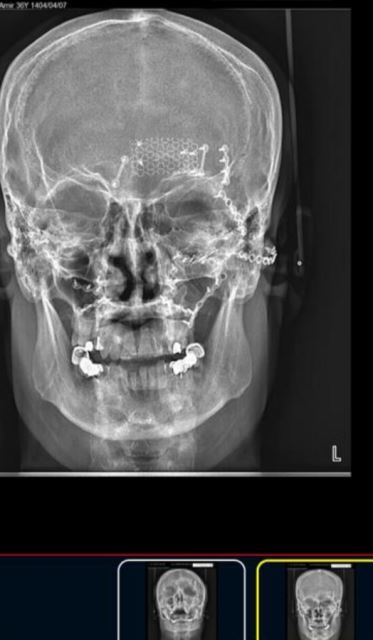

شکستگی متعدد صورت

بازسازی شکستگی صورت